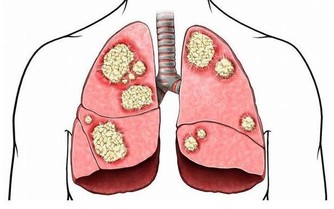

一般來說,除了看起來不雅之外,靜脈曲張通常不會帶來很大不便。但如果你不及時干預,它們確實有可能發展出一些並發症,包括腿部潰瘍、深靜脈血栓等。